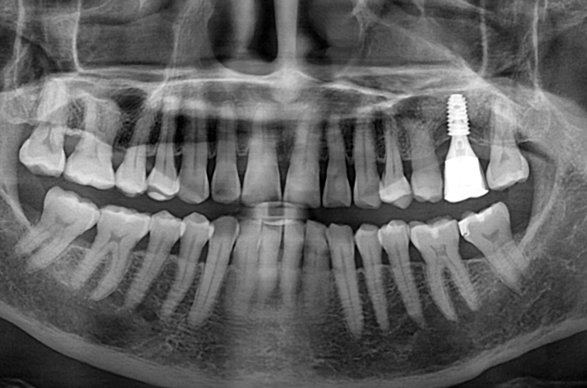

상악동 측방 거상술.

Before

발치를 너무 일찍하는 것도 아까운 일이지만,

너무 늦게 하면 소실된 잇몸 뼈는 더욱 회복하기가 어렵습니다.

때로는 적절한 시기에 발치하는 것이 가장 중요한 치료 시작의 첫 단추가 될 수 있습니다.

위 케이스는 이미 상악의 잇몸 뼈가 많이 부족하여

상악동 거상술을 시행하여 뼈이식을 충분히 시행한 후

임플란트 식립을 통해 보철을 완료하였습니다.